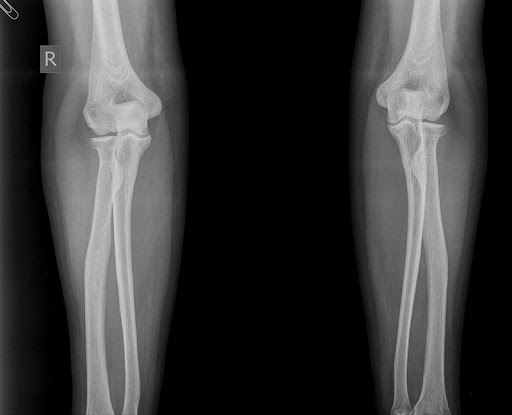

Рентгенография локтевых суставов в 2-х проекциях (со снимком)

Рентген локтевого сустава - диагностический метод, который позволяет получить снимок сочленения благодаря прохождению через него рентгеновских лучей.

Локтевой сустав — сложное соединение плечевой кости с лучевой и локтевой костями предплечья. В него входят сразу три простых сустава, связанные одной капсулой.